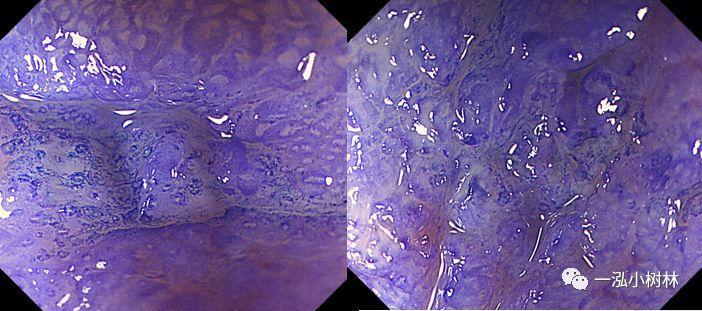

例1 胃窦病变

图1c NBI高倍放大:IMVP(+)、IMSP(+)、DL (+)

图4c NBI+ME:表面构造呈绒毛样,大小不等、形态不规则,边界清晰,诊断为0-IIc早期胃癌,分化程度:高分化腺癌(Tub1),深度:黏膜内。活检病理:高分化腺癌/高级别内瘤变。

图7 ME-NBI:不规则绒毛结构+不规则微血管结构+绒毛融合